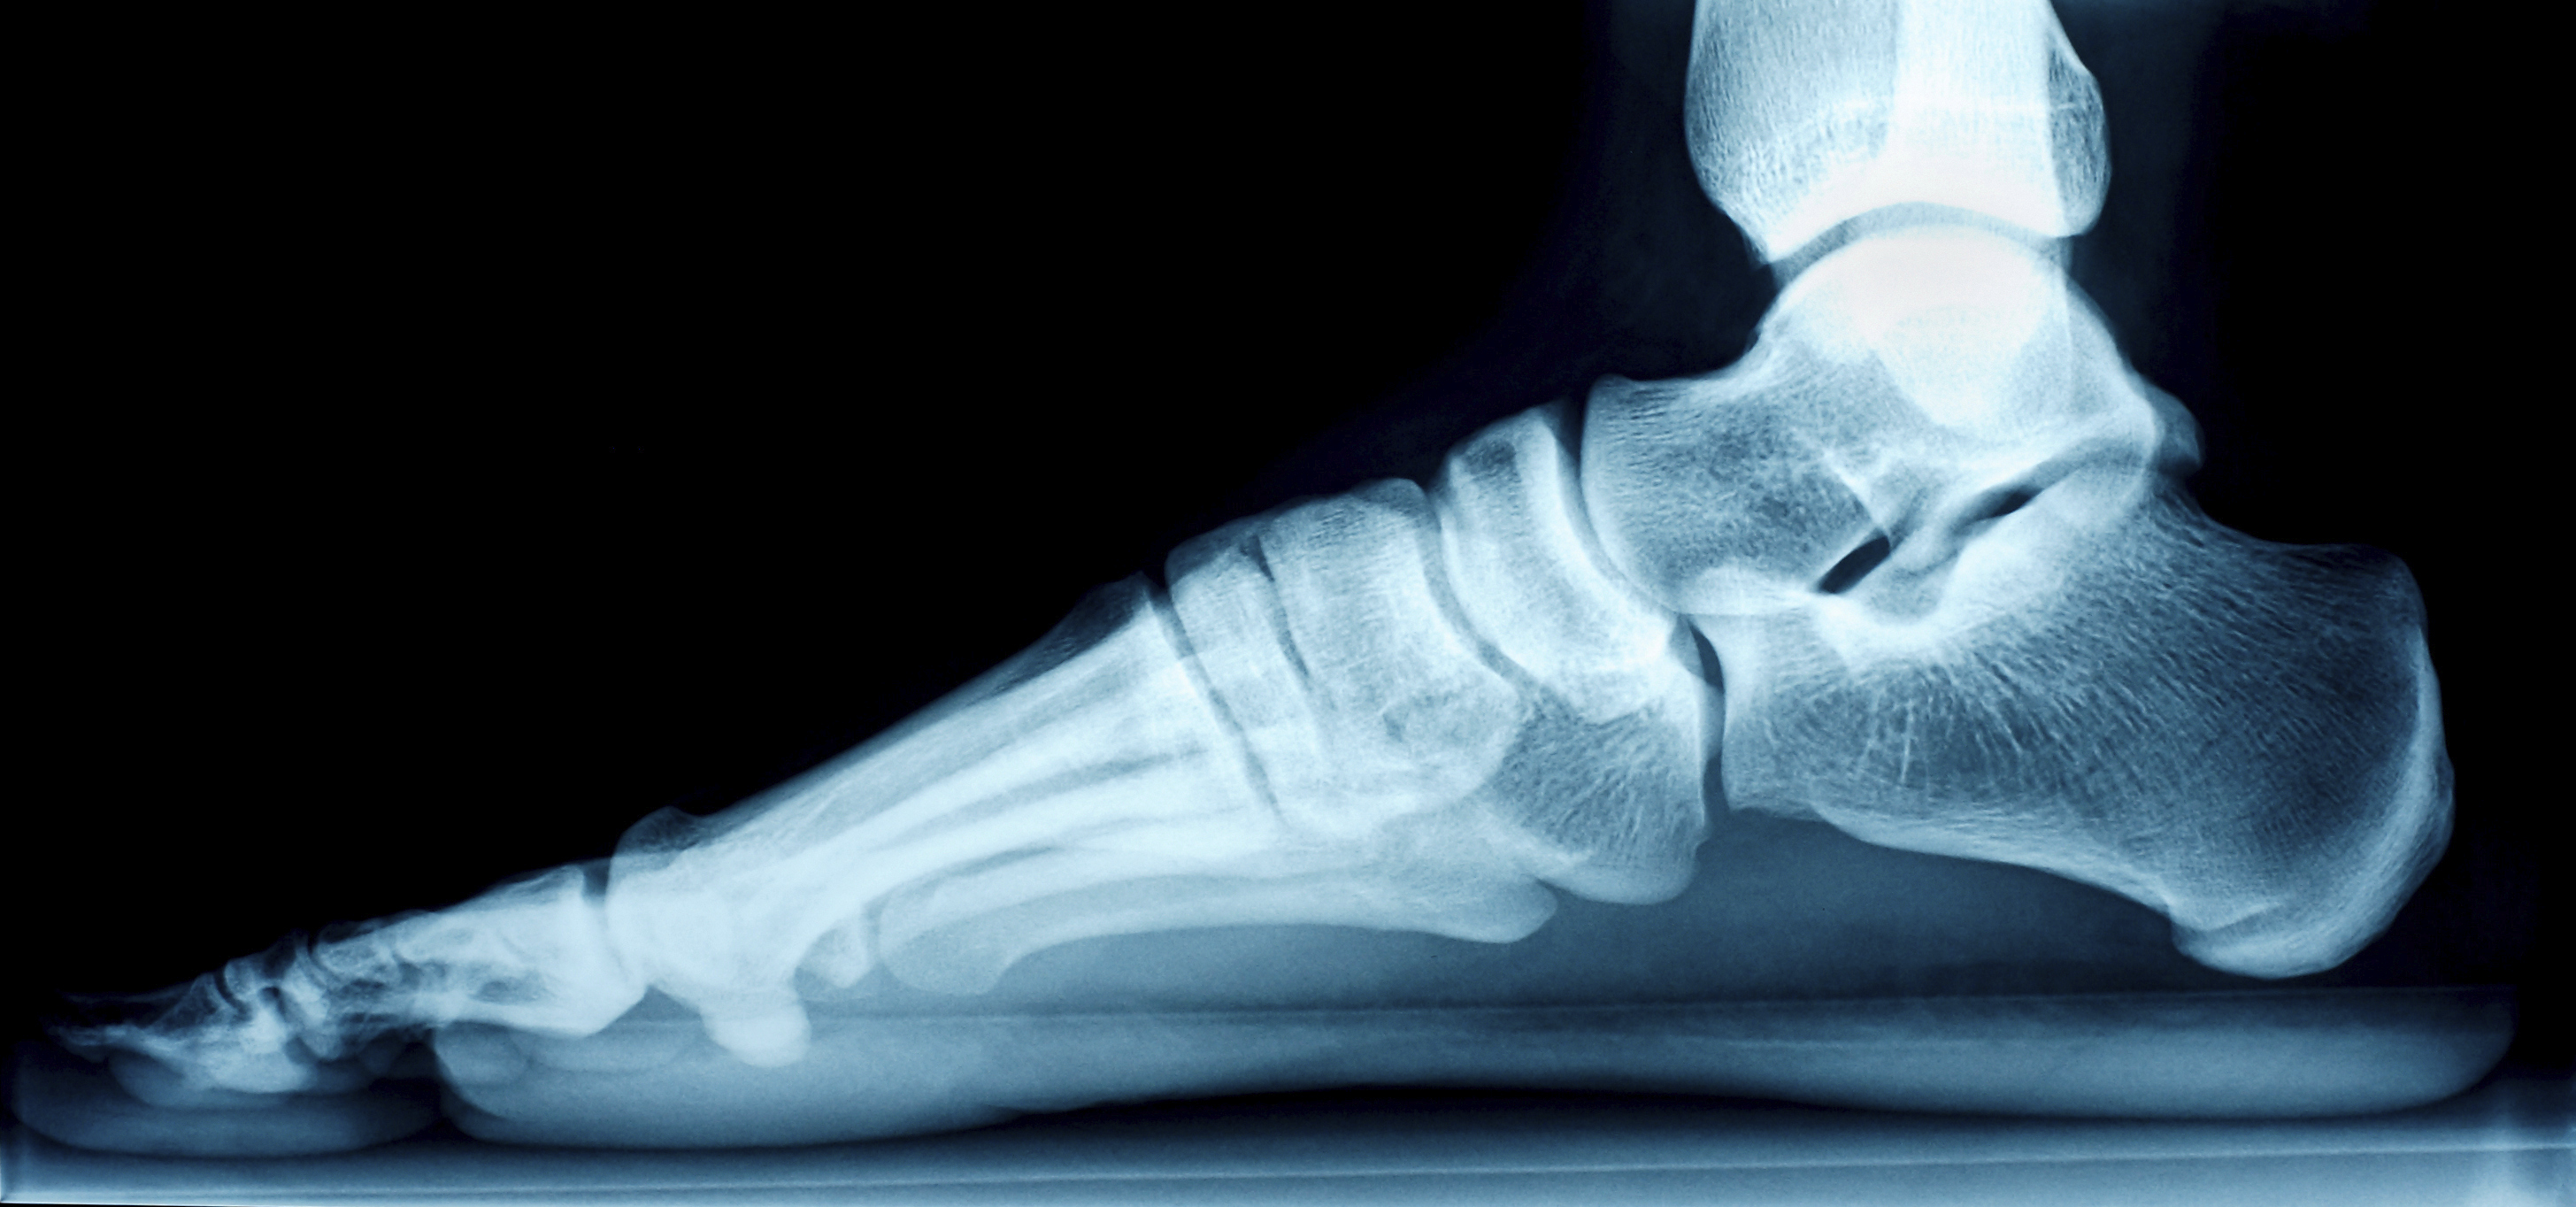

Come capire se si hanno i piedi piatti? Semplice! Se esaminate la superficie inferiore dei piedi, noterete che non tutta appoggia sul pavimento. Il piede, infatti, ha un’architettura molto simile a quella degli archi e delle volte architettoniche, con una volta plantare che si alza verso l’alto e 3 archi, detti archi plantari, che costituiscono la superficie esterna. Come negli archi e nelle volte degli edifici, gli archi plantari hanno il compito di trasformare le spinte verticali, proprie della posizione eretta e della locomozione, in spinte laterali, in modo da distribuire meglio il peso corporeo, visto che la superficie d’appoggio del nostro corpo, i piedi, appare davvero esigua.

Quando la volta plantare è molto bassa o il piede ne è privo e la pianta appoggia per terra, si ha la condizione del piede piatto [1].

piede